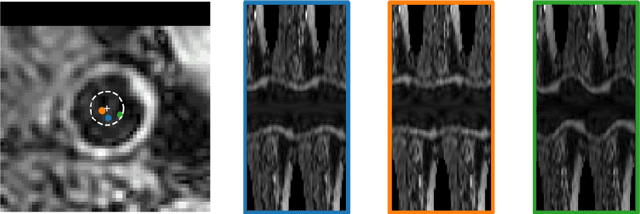

Abstract:The application of deep learning models to large-scale data sets requires means for automatic quality assurance. We have previously developed a fully automatic algorithm for carotid artery wall segmentation in black-blood MRI that we aim to apply to large-scale data sets. This method identifies nested artery walls in 3D patches centered on the carotid artery. In this study, we investigate to what extent the uncertainty in the model predictions for the contour location can serve as a surrogate for error detection and, consequently, automatic quality assurance. We express the quality of automatic segmentations using the Dice similarity coefficient. The uncertainty in the model's prediction is estimated using either Monte Carlo dropout or test-time data augmentation. We found that (1) including uncertainty measurements did not degrade the quality of the segmentations, (2) uncertainty metrics provide a good proxy of the quality of our contours if the center found during the first step is enclosed in the lumen of the carotid artery and (3) they could be used to detect low-quality segmentations at the participant level. This automatic quality assurance tool might enable the application of our model in large-scale data sets.